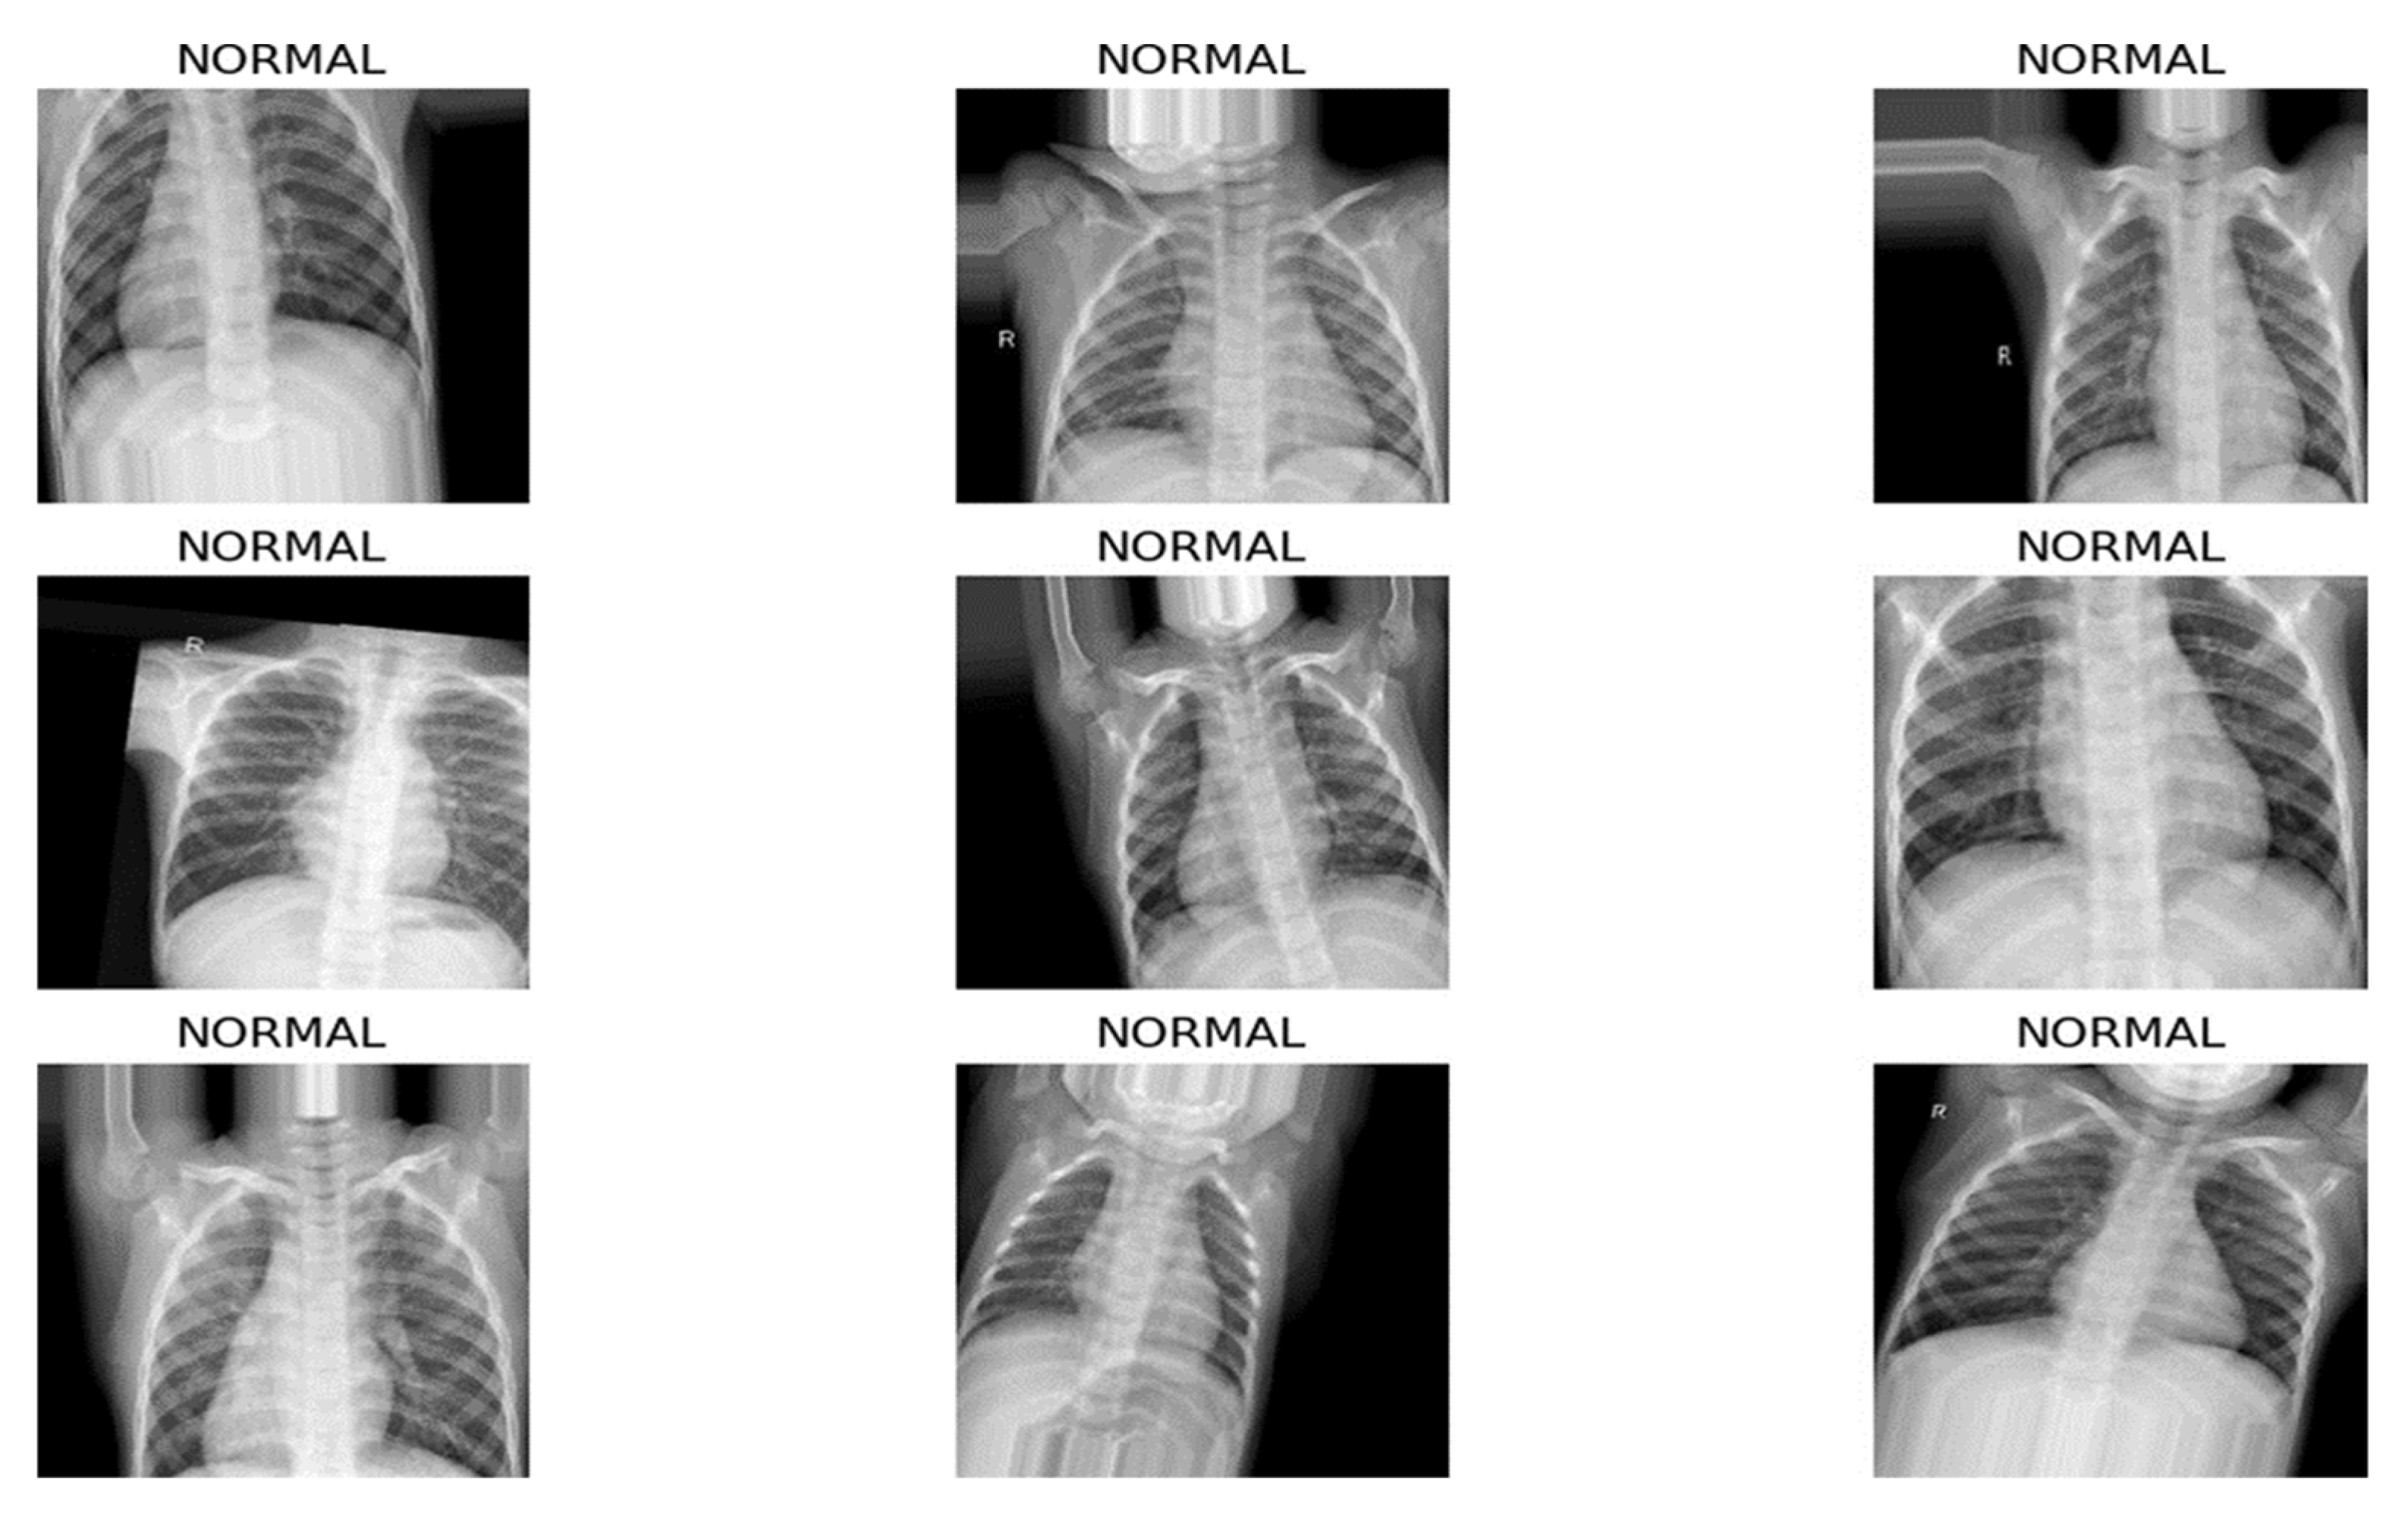

The dataset we chose to work with contains a large set of CXR images and was downloaded from Kaggle [30]. This dataset contains binary labels (‘Normal’ and ‘Pneumonia’) and does not differentiate between pneumonia subtypes such as bacterial, viral, fungal or atypical pneumonia. While this binary classification task is suitable for feasibility evaluation of an FL framework, it does not fully reflect the complexity of real-world clinical diagnosis. The CXR images from this dataset are anterior–posterior, meaning that the X-ray beam enters the body from the front (anterior) and exits through the back (posterior). The images are in JPEG format and have different dimensions (for example, 1782 × 1434, 1570 × 1164, etc.), but most of them have a high resolution (over 1000 pixels both in width and height). Their sizes range from 100 KB to 500 KB approximately, and they are labeled into two classes: normal and pneumonia. Some randomly selected images from the dataset are shown in Figure 2.